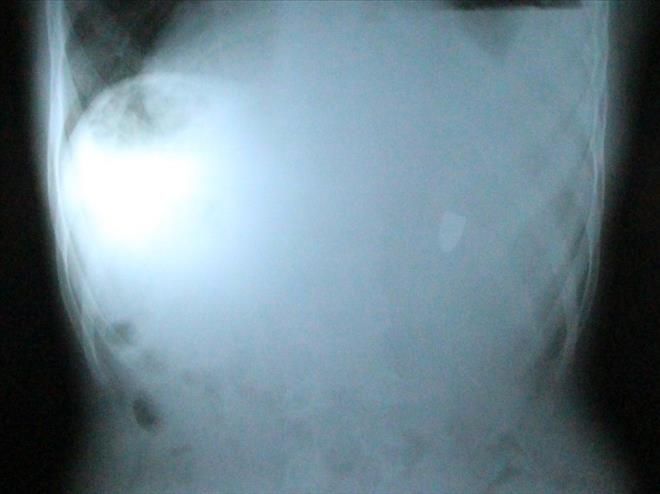

Nusaybin ilçesinde geçen hafta arkadaşlarıyla oyun oynadığı sırada tabaca mermisinin boynuna isabet ettiği Baver Keskin´in karnındaki mermi başarılı bir ameliyatla çıkarıldı.

Nusaybin devlet Hastanesindeki muayenesinden sonra Mardin Devlet Hastanesine kaldırılan Keskin, burada ameliyata alındı. Başarılı geçen ameliyatta Keskin´in karın boşluğundaki tabanca mermi çekirdeği olduğu yerden çıkarıldığı bildirildi.

Baver Keskin, geçen hafta Oğuzhan ilkokulunda arkadaşlarıyla oyun oynadığı sırada nereden geldiği belirlenemeyen bir tabaca mermisi çekirdeği boynundan karın boşluğuna girmişti. İlk muayenede tespit edilemeyen mermi, küçük çocuğun şikayetlerinin artması üzerine 4 gün sonra yapılan ikinci muayenede tespit edildiği ileri sürülmüştü.-Haber-Ahmet Akkuş